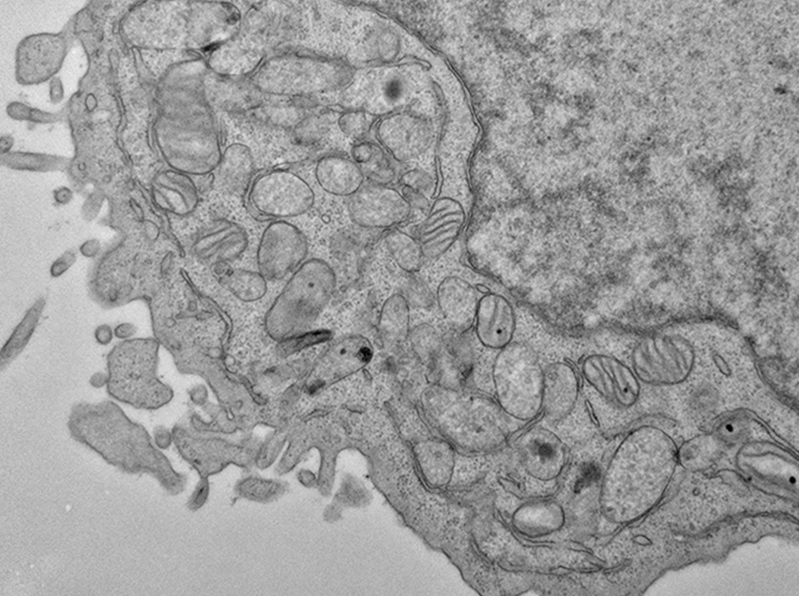

Electron microscopy image of a human hematopoietic stem cell showing hallmarks of ferroptosis, including shrunken mitochondria with fewer inner membrane folds.

Using genome editing, the researchers generated human HSCs with broken copies of the MYSM1 gene. The cells showed signs of stress, and produced less heme, a key iron-containing compound. They were also slower to produce proteins that could protect themselves against ferroptosis, and showed common signs of ferroptosis, such as shrunken mitochondria and certain lipid signatures, which were profiled by Clary Clish and others in Broad’s Metabolomics Platform. Moreover, the scientists found that shutting down ferroptosis in the cells prevented their death, suggesting that ferroptosis could underlie the loss of HSCs in this disease.